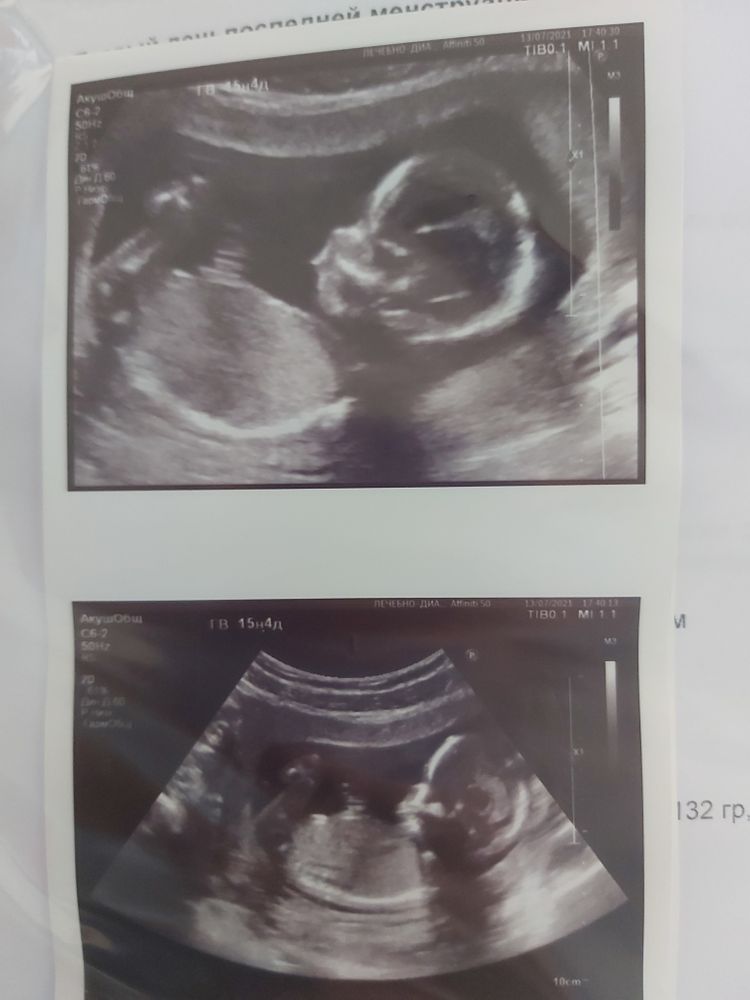

Фото для истории

Ну какова красота 😍 вот и у меня тонус, чтоб его... Сказали лечь и лежать. Видимо, завтра уйду на больничный 😒 хотя чувствую себя хорошо.

Снежана М., у меня был перенос эмбриончика после генетики,поэтому мы изначально знали что это девочка.на этом узи в 15 н 4 дня врач показала на экране что уже видно нашу мадам🙂

Анна Мартынова, 15 н 5 дней

Маленькая принцесса внутри мамы) Развивайтесь!